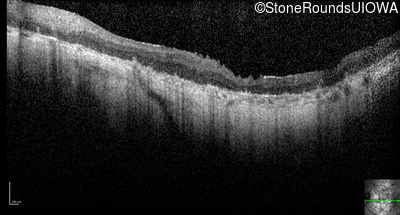

Optical Coherence Tomography - Right - Hand Motion 1' sc

Exemplar / OCT Stack

OCT Stack

Optical Coherence Tomography - Left - Hand Motion 1' sc